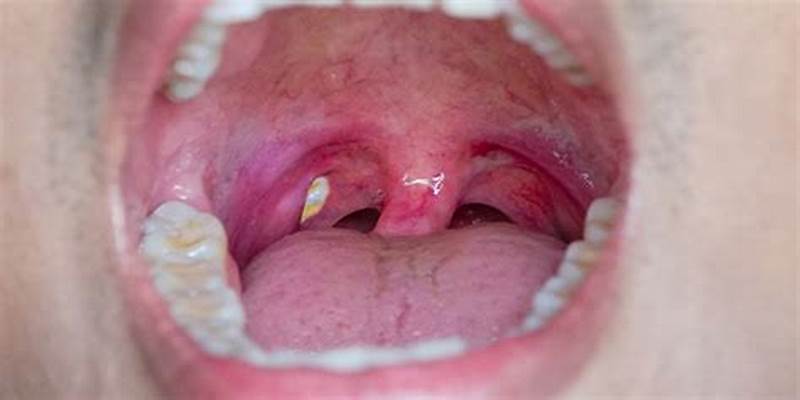

편도결석이란 편도결석은 편도에 생기는 작은 돌 같은 덩어리로, 편도내 세균, 단백질, 칼슘 등이 결합하여 생성됩니다. 이 글에서는 편도결석이 생기는 이유, 확인법, 증상, 냄새 방지법, 제거법, 가글법, 그리고 치료법에 대해 자세히 알아보겠습니다.

편도결석 확인법

편도결석을 확인하는 방법은 다음과 같습니다.

1. 양치질과 가글

양치질이나 가글을 한 후, 거울을 보면서 목구멍을 살펴봅니다.

2. 혀를 사용한 확인

편도결석은 주로 편도의 맨 앞쪽에 생기기 때문에, 혀를 뒤로 내밀어 편도를 확인하면 쉽게 발견할 수 있습니다.